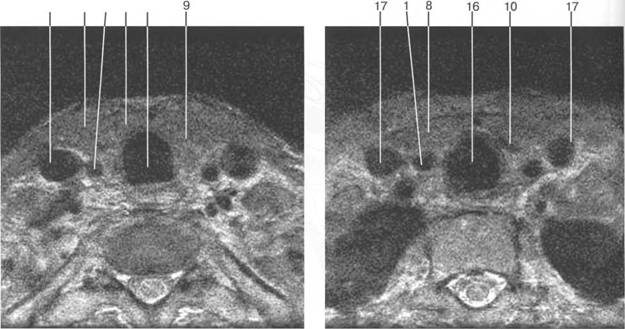

m. longus coli; 1 sternocleidomastoideus; sternohyoideus; sterno-thiroideus; thyreoideus; platysma; fascia coli profunda; m. longus capitis; m. scalenius anterior; m scalenius medius; m. scalenius posterior; a. facialis; a. lingualis; a. thyreoideus superior; cartilago cricoidea; cartilago thiroidea.

17

железы при поперечном сканировании.

[W. Swobodnic, M.Herrmann].

17 8 1 7 16 |